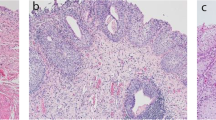

Histological features of control and BOO rats. (a) Bladder weight, (b) body weight, and (c) bladder weight to body weight ratio of control and 6-wk-old BOO rats. (d) Left: HE staining. Middle: Masson’s trichrome staining. Magnification 200 × . Red areas indicate smooth muscle, and blue areas indicate connective tissue. In the control group, only a small amount of pale blue collagen deposition was observed between muscle bundles, and the 6-wk-old BOO group showed increased collagen deposition and connective tissue. Right: Sirius Red staining, swollen smooth muscle (light yellow), and increased collagen fibres (red) appeared in the 6-wk-old BOO group. The (e) mRNA and (f ) protein expression levels of TGFβ2 in bladder tissue of rats in the control and 6-wk-old BOO groups. The data are presented as the mean ± SD; *P < 0.05, **P < 0.01, ****P < 0.0001 using the Student’s t-test.

To further determine whether BOO led to bladder wall hypertrophy and fibre formation, we performed HE, Masson’s trichrome, and Sirius Red staining to facilitate histological analysis. The bladder tissue of the control group only exhibited sparse light-blue staining of collagen fibres between the smooth muscle bundles. In the BOO group, the degree of collagen fiber deposition and interstitial tissue fibrosis increased significantly (Fig. 3d).